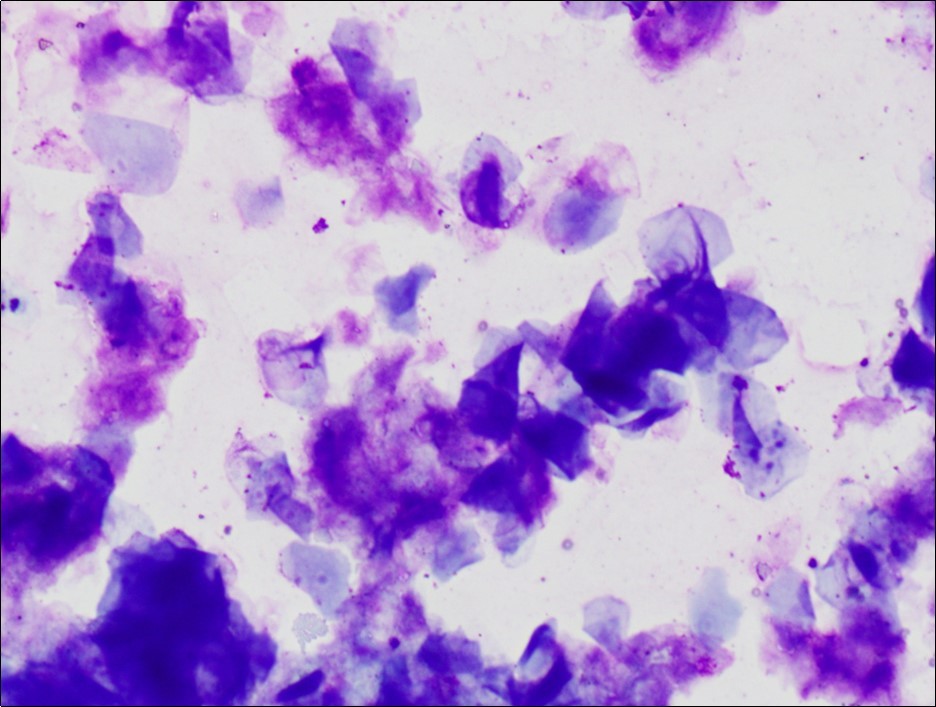

On physical exam, a well-defined cystic swelling of 10 x 4 cm size was palpable in the left scrotum (Figure 1). It was non tender and mobile within the subcutaneous tissue, with left testis palpable separately from the swelling. Trans-illumination test was negative. Scrotal ultrasound revealed a uniform, hypoechoic left extra-testicular lesion which appeared to be avascular. Alpha-fetoprotein (αFP) and beta-human chorionic gonadotropin (β-hCG) analyses were within normal limits. Fine needle aspiration revealed thick aspirate with cytological features suggestive of keratinous cyst (Figure 2).